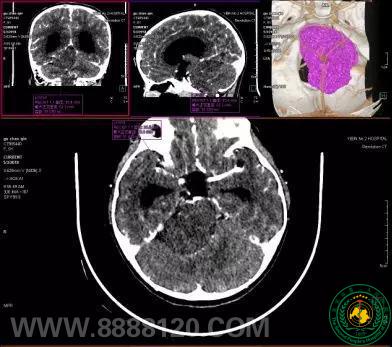

宜宾市第二人民医院扶贫记之神经外科篇

宜宾市第二人民医院 图文